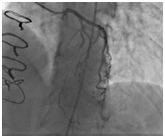

The available data suggest that surgical therapy appears to be safe, beneficial and effective (Figures 1 & 2). Surgery may be recommended in the very rare cases of severely symptomatic patients who are refractory to medical therapy, or when PCI has failed.48,49 Non-pharmacological therapy, namely, surgical intervention and percutaneous coronary intervention should only be considered as a therapeutic option in patients with MB refractory to medical therapy and documented myocardial ischemia, with the expectation that revascularization rates will be high even with drug-eluting stents.

Figure 1 Snapshot of the preoperative coronary angiogram at systole showing compression of the proximal and mid-segments of the LAD. Reprinted with permission from Mok S, Majdalany D, Pettersson GB. Extensive unroofing of myocardial bridge: A case report and literature review. SAGE Open Medical Case Reports 2019;7:1-3.

Figure 2 Snapshot of the postoperative coronary angiogram showing resolution of any compression of the LAD. Reprinted with permission from Mok S, Majdalany D, Pettersson GB. Extensive unroofing of myocardial bridge: A case report and literature review. SAGE Open Medical Case Reports 2019;7:1-3.